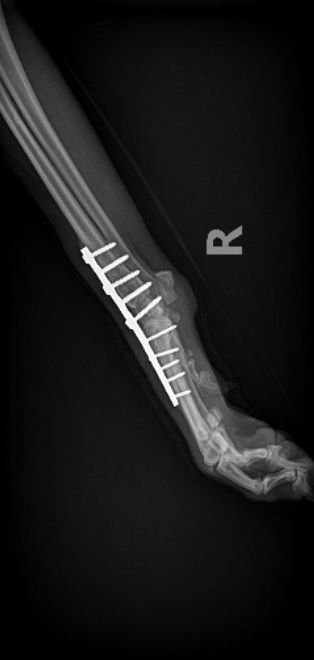

ADVANCED VETERINARY ORTHOPEDIC SERVICES

Our world-class, board-certified veterinary surgeons are dedicated to providing the most advanced canine orthopedic veterinary surgery and musculoskeletal assessment to ensure your beloved pet receives the most appropriate and comprehensive veterinary treatment available.